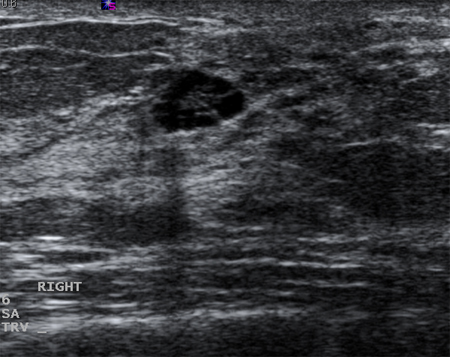

Cysts that recur or do not completely resolve with aspiration should be biopsied to rule out malignancy. Similarly, biopsy should be considered in complex cysts or those with solid elements. Sonographic characteristics may classify a solid mass as either "probably benign" or "suspicious." Masses that are smooth, oval, lobulated, with clearly defined margins, and that are wider than they are tall, are often benign (e.g., fibroadenoma). If a mass is irregular, heterogeneous, has poorly defined or spiculated margins, and is taller than it is wide, it is considered "suspicious" for malignancy, and biopsy should be undertaken.[Figure caption and citation for the preceding image starts]: Ultrasonographic image of a complex cystCourtesy of Dr Lane Roland, University of Louisville; used with permission [Citation ends].